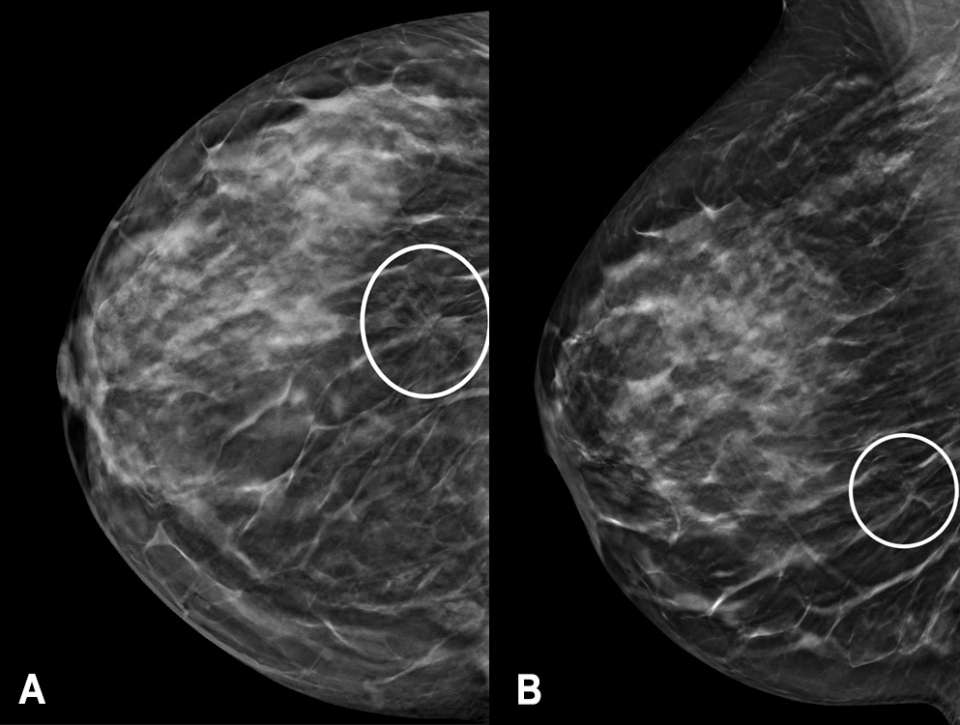

Diagnostic mammography followed one month thereafter and included spot compression views of the area of architectural distortion in the right breast (Figure 2A). Targeted breast ultrasonography showed a vague hypoechoic area measuring up to 11 mm, which correlated with the mammographic findings (Figure 2B). The finding was categorized as BI-RADS 4B, and an ultrasound-guided biopsy was recommended.

Figure 2: (A) Diagnostic right breast mammography and (B) right breast ultrasound of the same patient. There is a persistent architectural distortion on spot compression mammography in the lower outer quadrant, seen both on CC (circled) and mediolateral (not pictured) views. Targeted ultrasonography showed a vague hypoechoic area (arrow) measuring 11 x 7 x 6 mm at 7 o’clock, 9 cm from the nipple, correlating with the mammographic finding. The finding was classified as a BI-RADS Category 4B and ultrasound-guided biopsy was recommended.